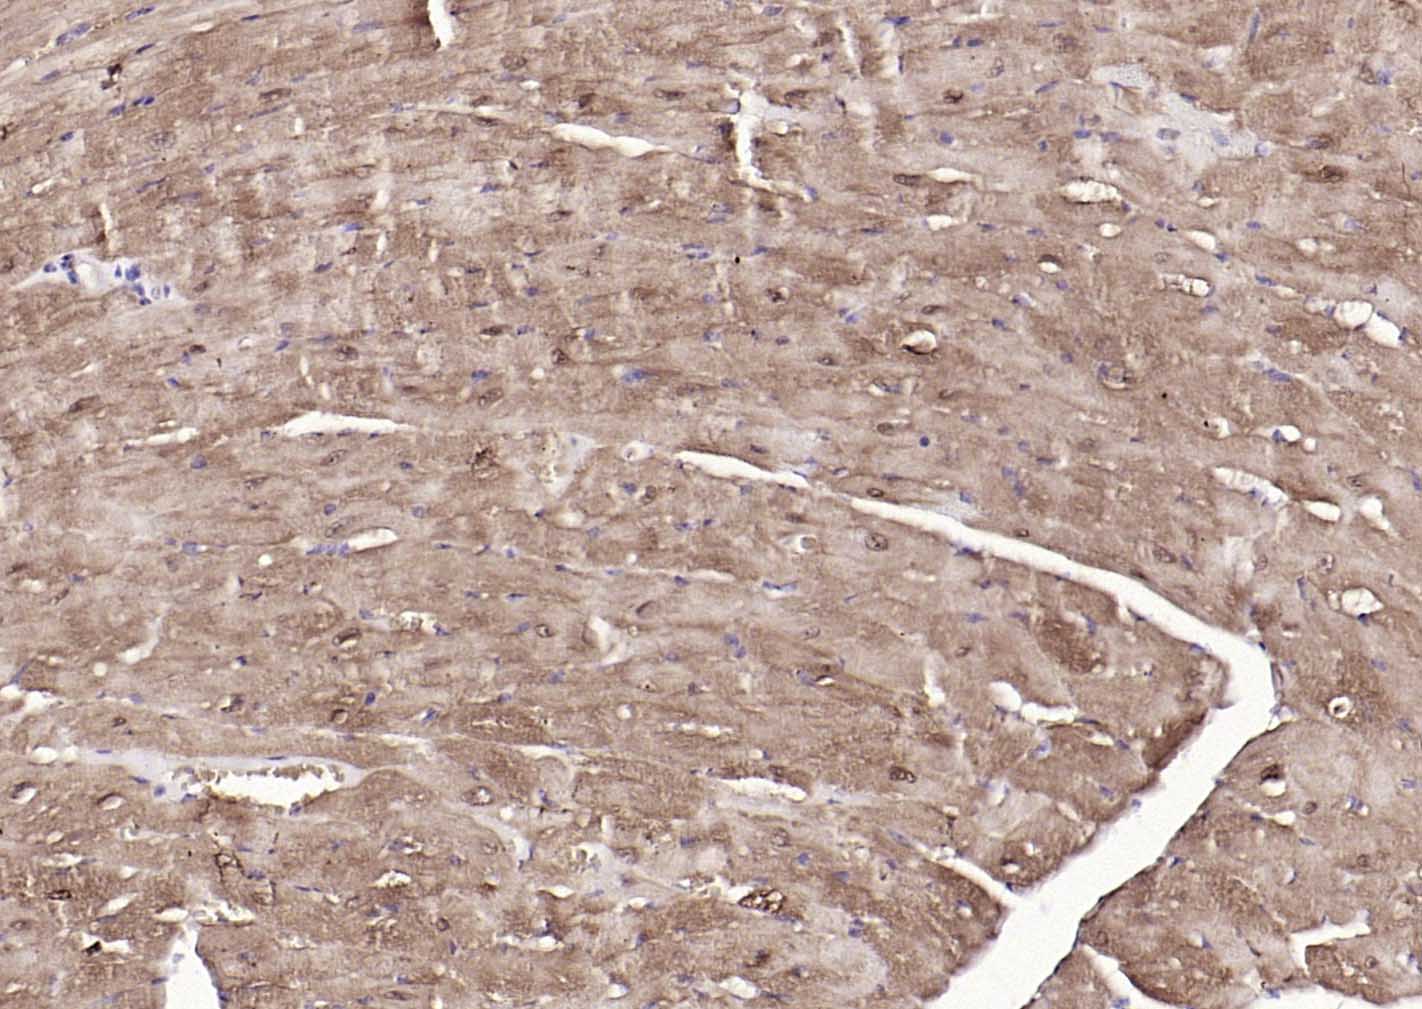

Paraformaldehyde-fixed, paraffin embedded (human heart); Antigen retrieval by boiling in sodium citrate buffer (pH6.0) for 15min; Block endogenous peroxidase by 3% hydrogen peroxide for 20 minutes; Blocking buffer (normal goat serum) at 37°C for 30min; Incubation with (S100A1 ) Polyclonal Antibody, Unconjugated (bs-41209R) at 1:200 overnight at 4°C, followed by operating according to SP Kit(Rabbit) (sp-0023) instructionsand DAB staining.